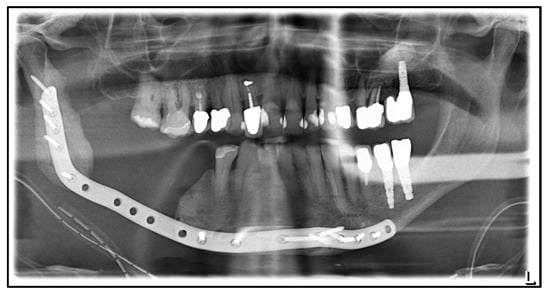

| July 2014: | Diagnosis of MRONJ in the right molar region of the mandible. Following mandibular box resection and protective plate osteosynthesis with a patient-specific plate. |

| June 2017: | Removal of the reconstruction plate in the right mandible, re-osteosynthesis, and excision of a submandibular fistula on the right. |

| August 2018: | Partial mandibular resection with continuity defect and alloplastic reconstruction using a patient-specific plate, excision of a submental fistula |